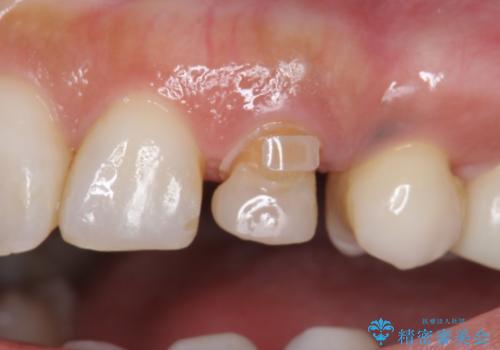

治療途中

終了時

左:虫歯を除去したところ。遠心が歯ぐきより深い状態です。中:そのままかぶせようとすると、遠心が歯ぐきが腫れやすい状態です。右:エクストリュージョンをしたことで、遠心の歯ぐきの腫れが収まっていることがわかります。